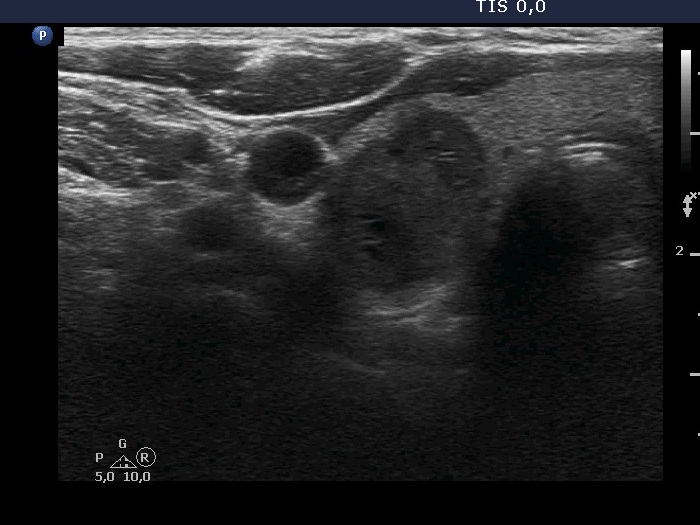

Extrathyroidal spread - case 2116 (ultrasonographic picture 4)

Right lobe, another transverse scan. The lesion presents different echogenicities. This difference raises the possibility that the lesion is composed of more nodules.